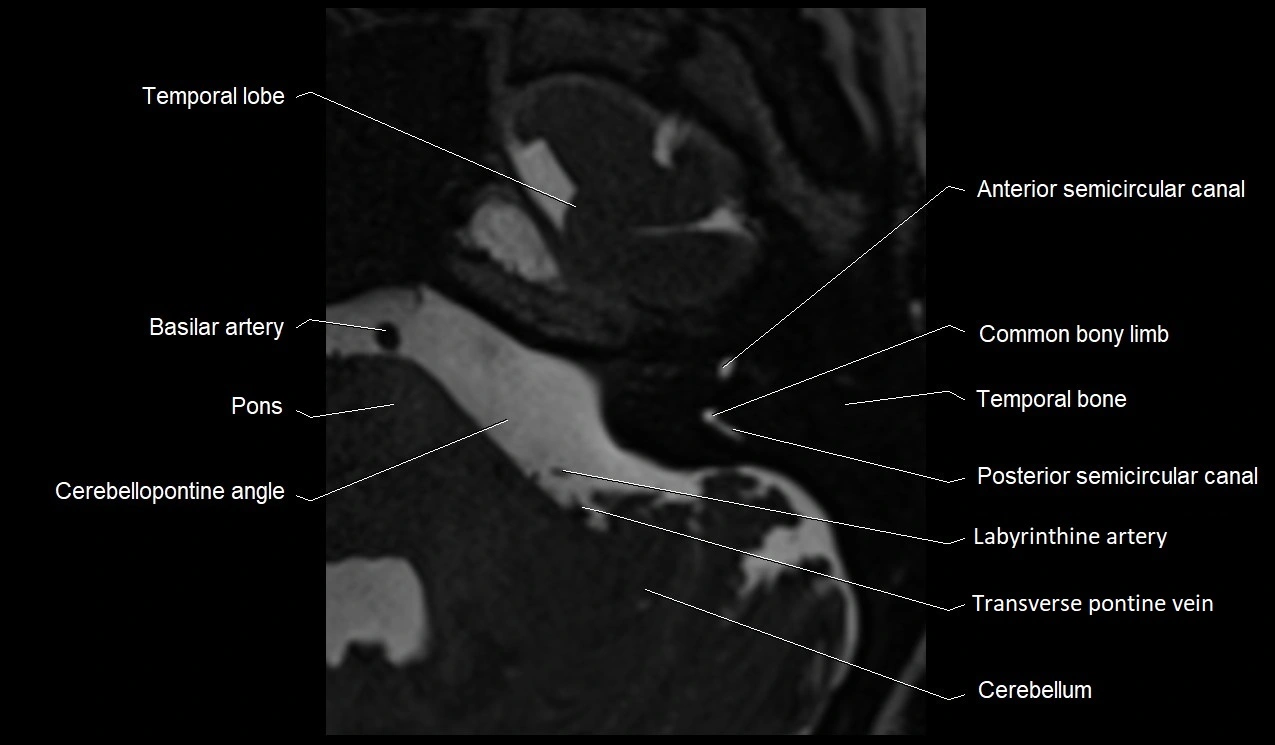

MRI images

image